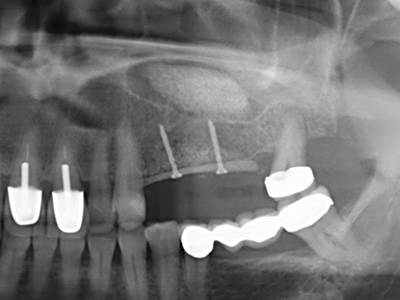

Fig. 11: The postoperative panoramic image shows the vertical augmentation and sinus floor elevation.

Fig. 24: Application of the distractor (TRACK-System, KLS Martin).

Fig. 25: Panoramic image after reaching the final distraction height, before consolidation period.